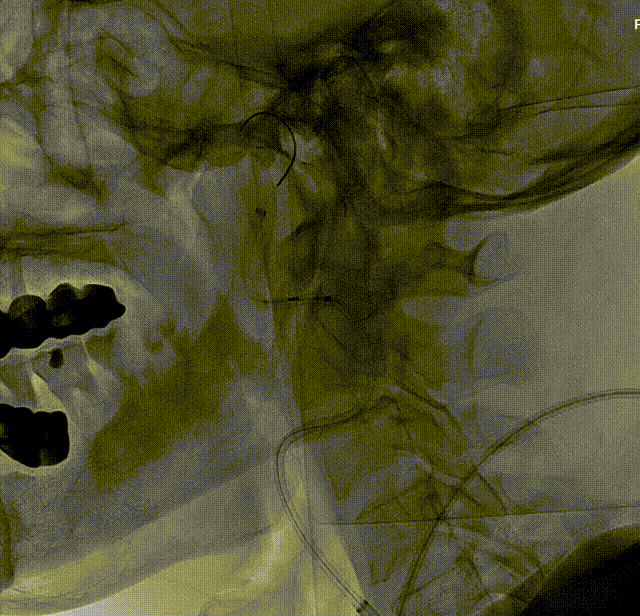

考虑到靶血管较迂曲,拟使用中间导管进行支架释放。在Workhorse导丝引导下,将中间导管通过迂曲段,经由中间导管送入8mm*40mm颈动脉支架至右侧颈内动脉狭窄处。回撤中间导管至颈总动脉后,在透视状态下准确释放支架。

造影显示残余狭窄小于30%,未进行后扩张。术后造影显示狭窄解除,支架置入部位满意,血流较术前明显改善。使用中间导管将Nav6保护伞顺利回收后,对股动脉穿刺点进行止血,患者安返病房。